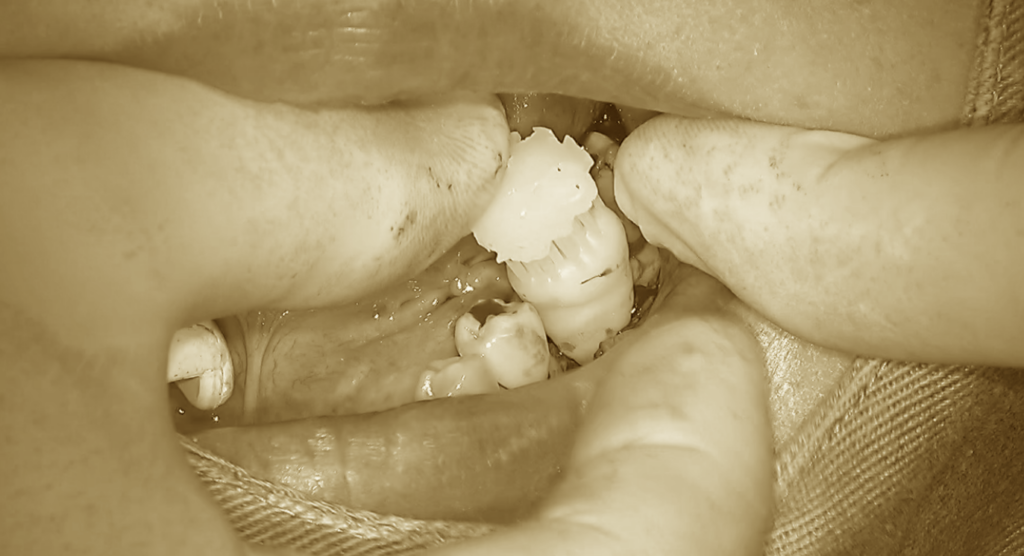

ある程度、移植歯が入るサイズまで形成できた段階で、

歯牙レプリカを用いた試適を行います。

歯牙レプリカとは、

CTデータから移植予定の歯の形態を再現し、

3Dプリンターで作製した模型です。

これにより、実際の歯を使用することなく、

適合状態や方向の確認が可能になります。